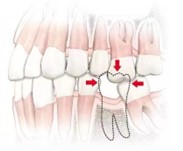

1.影响结构

缺牙较长时间后,两边的牙会向中间倒,容易出现塞牙的情况。严重时导致全口牙排列不齐,咬合紊乱。余留牙所承担的压力过重,致使牙周组织因创伤,导致牙齿松动、脱落。